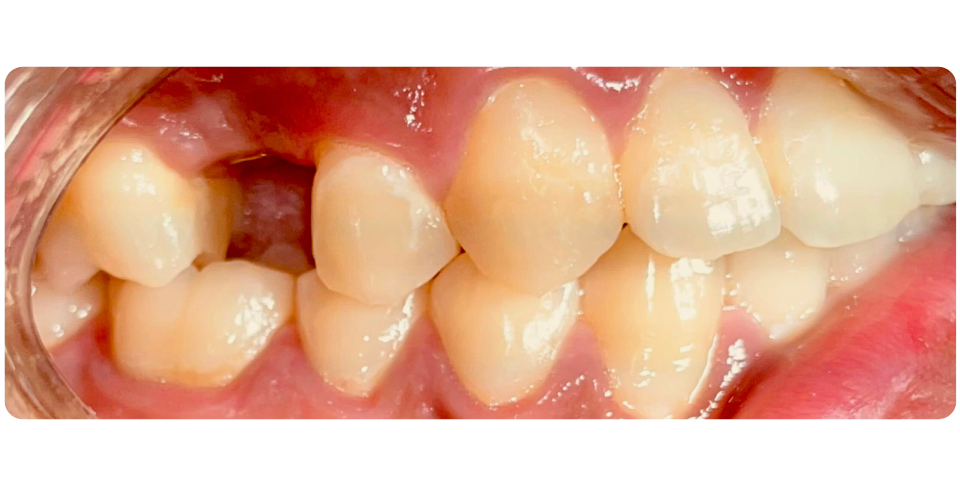

Conventional Implants

Dental implants are artificial tooth roots that are surgically placed into the jawbone to replace missing tooth or teeth.

They are typically made of titanium or a titanium alloy, which fuses with the bone over time in a process called osseointegration, providing a stable and durable foundation for replacement teeth, such as crowns, bridges, or dentures.

They are the best way to replace missing teeth, replacing the old concept of dental bridges which damages the adjacent teeth to replace a tooth or teeth.